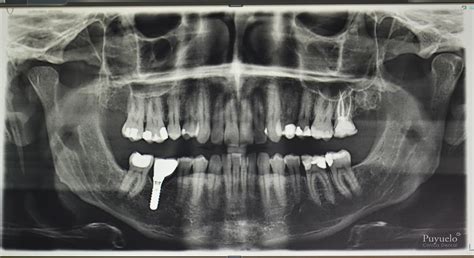

La ortopantomografía, también conocida como radiografía panorámica dental, es una técnica radiológica fundamental en la odontología moderna. Permite obtener una imagen completa de los dientes, la mandíbula y el maxilar, siendo esencial para el diagnóstico en diversas especialidades como la cirugía oral, implantología, ortodoncia y periodoncia. Este post te actualizará sobre las diversas aplicaciones de la OPG, las estructuras observables, cómo obtener una imagen perfecta, evitar errores comunes y te ayudará a decidir si un equipo de rayos X panorámico o un CBCT es la mejor opción para tu clínica dental.

Una ortopantomografía de calidad revela una serie de estructuras anatómicas clave:

Dientes

La dentición debe mostrar una curva suave en la línea de sonrisa, con un espacio claramente distinguible entre los dientes superiores e inferiores. Los dientes posteriores deben tener un tamaño normal y la superposición entre premolares debe ser mínima. Las coronas de los dientes anteriores deben ser visibles y sus ápices completos.

Senos y Nariz

Los tejidos blandos de la nariz y sus cartílagos deben ser claramente visibles. La sombra del paladar duro debe ser notoria, y es posible observar imágenes fantasma del paladar en los senos maxilares. La lengua debe aparecer en contacto con el paladar en la imagen.

Cóndilos Mandibulares

Ambos cóndilos mandibulares deben aparecer centrados en la imagen, con un tamaño y altura similares en relación al plano horizontal.

Rama de la Mandíbula y Columna Cervical

La rama mandibular debe ser simétrica en ambos lados de la imagen. Si la columna vertebral es visible, no debe superponerse a la rama mandibular, y la distancia entre ambas debe ser igual en ambos lados.

Cuerpo Mandibular

La corteza inferior de la mandíbula debe presentar una imagen uniforme y continua. No deben existir imágenes fantasma o dobles imágenes del hueso hioides, y la línea media de la mandíbula y el maxilar no deben estar aumentadas.

Diagnóstico de Patologías

La radiografía panorámica permite detectar problemas y patologías que no son visibles a simple vista, como:

- Caries: la enfermedad bucodental más común.

- Periodontitis o piorrea: la segunda patología más frecuente.

- Infecciones, quistes, fracturas óseas.

- Dientes no erupcionados o retenidos.

- Maloclusiones dentales.

La detección temprana de estos problemas puede llevar a tratamientos menos invasivos y más económicos a largo plazo.